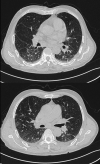

Patient concerns: A 76-year-old male of peculiar skin infection. Metagenomic Next Generation Sequencing and bacterial culture of skin secretions revealed M marseillense. To the best of our knowledge, we report the first patient diagnosed with disseminated M marseillense infection. Here, we identified only 8 other reports of patients with M marseillense infection.

Diagnoses: Disseminated M marseillense infection.